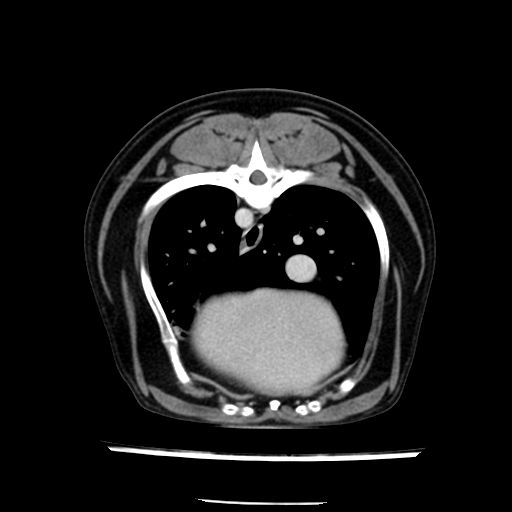

prescritto esame TAC

sequenza immagini limitata al fegato reni e surreni

le immagini ecografiche rispetto alla tac datano circa 7 mesi prima ,le surrenali sono normali nonostante il test acth sia risultato positivo .all’esame TAC dopo diversi mesi risultano aumentate armonicamente nel volume e si individua un forte sospetto di adenoma ipofisario .

sospetto adenoma ipofisario vs. meno probabilmente meningioma della base; intertiziopatia polmonare; lesione espansiva epatica, verosimilmente del lobo laterale sinistro, di sospetta natura neoplastica; lesioni spleniche di natura da definire; iperplasia/ipertrofia delle ghiandole surrenali, bilateralmente; vertebra di transizione del rachide toracico; tenosinovite cronica del muscolo bicipite brachiale di destra.

- l’esame tac e’ stato eseguito circa quattro mesi dopo la prima ecografia che non aveva messo in evidenza aumento del volume surrenalico (vedi immagini) ma solo la lesione epatica, la presenza di PU PD aveva portato ad un controllo per l’ ipercorticosurrenalismo confermato dal test act , in questo caso, si deduce che i sintomi di ipercorticosurrenalismo legati all’adenoma sono comparsi prima delle modificazioni surrenaliche, quindi in caso di sospetto ,a mio avviso e’ buona norma eseguire prima il test di stimolazione e dopo L’ECOGRAFIA per tentare una classificazione eziopatogenetica . La Tac si e’ quindi dimostrata molto valida in sensibilita’ e specificita’ riguardo la patologia surrenalica in quanto in grado di vedere o fortemente sospettare (ovviamente meno sensibile della RM) un piccolo adenoma ipofisario e le alterazioni morfovolumetriche della surrenale.

- Nessuna informazione diversa per quello che riguarda l’esame ecografico del fegato e la presa del contrasto si confermano le lesioni individuate e l’ipoenanchement in fase portale.

- la total body permette di escludere metastasi e di avvicinarsi all’interventistica

la tac dopo 7 mesi permette misure tridimensionali 5,2 x 9,2 x 4,5 cm (forma piu’ allungata )